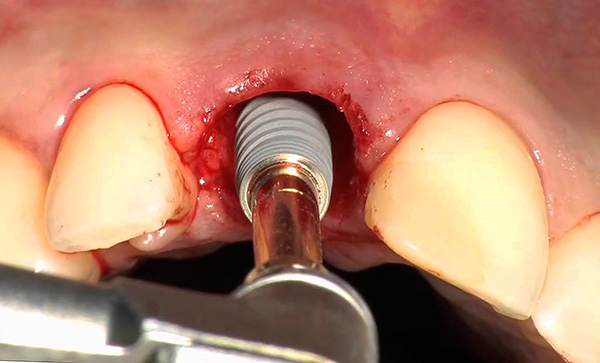

Le fotografie seguenti mostrano un esempio di impianto di un dente anteriore appena rimosso (che si è rotto da una lesione meccanica):

nota

In alcune situazioni, quando le condizioni del tessuto osseo lo consentono e l'impianto ha una fissazione primaria abbastanza buona, è possibile installare una corona in metallo-plastica economica per il periodo di osteointegrazione dell'impianto. Per i denti anteriori, questo è particolarmente importante, poiché consente di ripristinare l'estetica della dentatura in modalità express. Considerando che i denti anteriori non sono coinvolti nella masticazione del cibo, il carico sull'impianto sarà minimo.